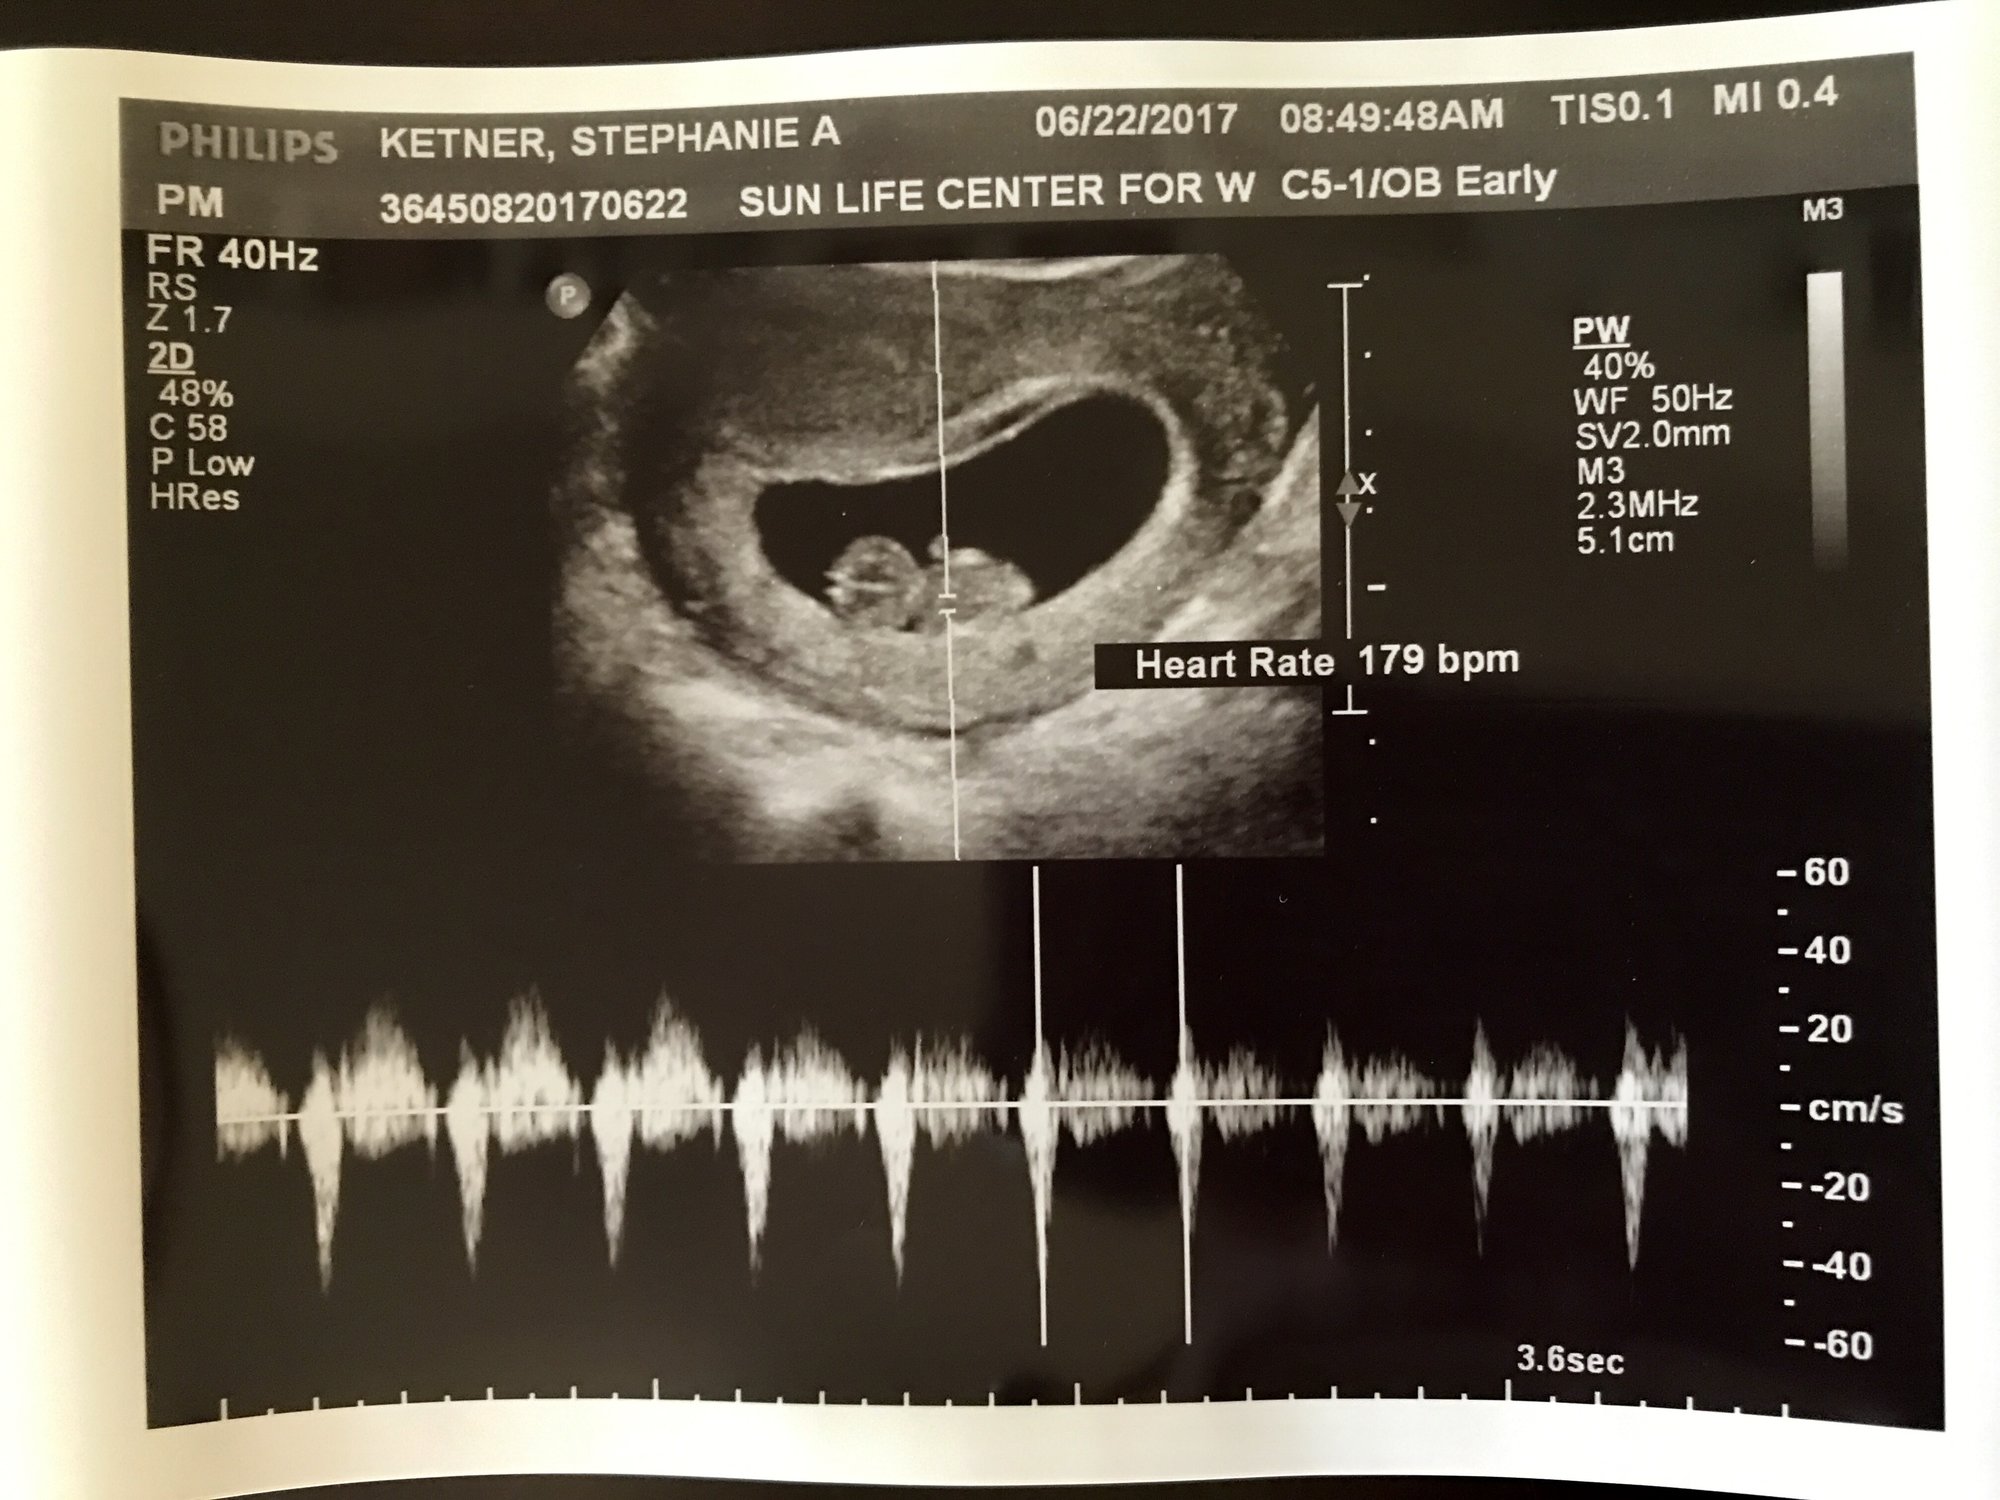

Had my first appointment this morning! I'm 9w6d due January 19. Having some fun trying to figure out old wives tales. According to the heart rate, if it's above 140 bpm it's a girl. And trying to make sense of Ramzi method and if I'm reading that right, that also says girl. Chinese gender predictor chart says boy though. I love old wives tales. So fun!

Had my second ultrasound on Wednesday for my rainbow baby. I measured a week late at my first ultrasound ultrasound and now only measured 4 days behind! Baby measured 9w 3d and had a heart rate of 179! Baby was moving their little legs all over!